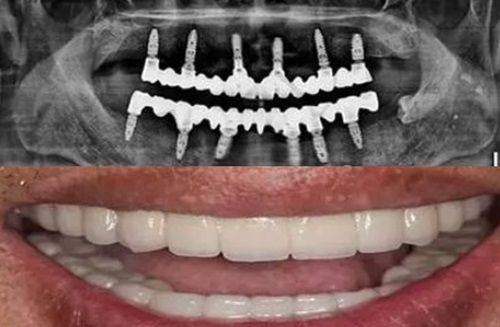

有部分项目通常被归类为美容或特需服务,不在医疗保险报销范围内,需要患者自费。例如种植牙,由于材料成本高且属美容性质,湖南湘西地区明确不纳入医疗保险。牙齿矫正,包括金属矫正、隐形矫正等正畸治疗也不能报销。美容修复项目,如烤瓷牙、牙齿美白、冷光美白等同样不在报销行列。还有保健类项目,像常规洗牙、涂氟、窝沟封闭等预防性服务也需患者自行承担费用。这些项目更多是为了提升口腔美观度或进行预防保健,所以不在医疗保险报销范围内。

湘西口腔医院作为医疗保险定点单位,为患者提供了诸多便利。一方面,使用医疗保险支付符合报销条件的费用,大大减轻了患者的经济负担,让更多人能够享受到优质的口腔医疗服务。另一方面,医院积极响应医疗保险政策,不断优化服务流程,提高报销效率。例如,在患者就诊时,医院工作人员会详细告知医疗保险报销的相关事宜,帮助患者准备所需材料。此外,对于一些特殊疾病,如颌面外科手术等可按住院比例报销,若患者是职工医疗保险,报销比例更高能达到70%。同时,医院还开展儿童免费涂氟、社区义诊等公益项目,体现了其社会职责和对患者的关怀。